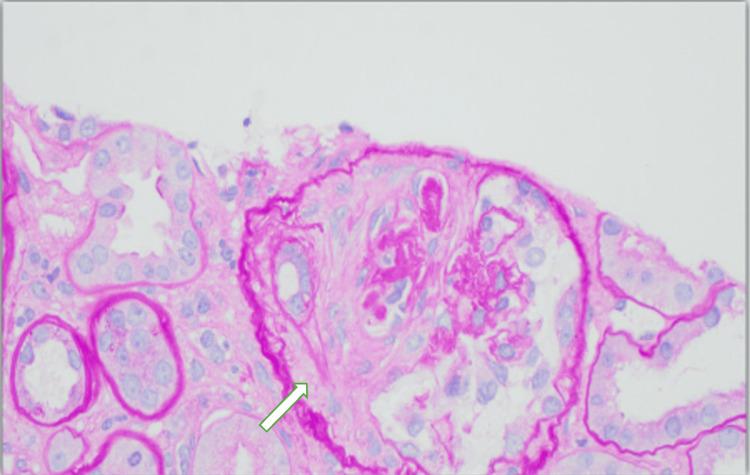

We present a rare case of hydralazine-induced antineutrophil cytoplasmic antibody (ANCA) vasculitis and lupus, characterized by the simultaneous and severe involvement of multiple organ systems. Following outpatient hydralazine dose escalation, a 77-year-old woman developed hypoxic respiratory failure secondary to diffuse alveolar hemorrhage, acute kidney injury with crescentic glomerulonephritis, and pancytopenia. Serologic testing revealed positive antinuclear antibody (ANA), dsDNA, anti-histone antibody, and P-ANCA, supporting the diagnosis of drug-induced autoimmune syndrome. This case highlights the risk for severe multi-organ dysfunction in drug-induced lupus and vasculitis, emphasizing the need for vigilance in recognizing such complications.

我们报告一例罕见的由肼屈嗪诱发的抗中性粒细胞胞浆抗体(ANCA)血管炎和狼疮病例,其特征为多个器官系统同时且严重受累。在门诊逐步增加肼屈嗪剂量后,一名77岁女性出现了因弥漫性肺泡出血继发的低氧性呼吸衰竭、伴有新月体性肾小球肾炎的急性肾损伤以及全血细胞减少。血清学检测显示抗核抗体(ANA)、双链DNA、抗组蛋白抗体和P-ANCA呈阳性,支持药物诱发的自身免疫综合征的诊断。该病例突出了药物诱发的狼疮和血管炎中严重多器官功能障碍的风险,强调了在识别此类并发症时保持警惕的必要性。